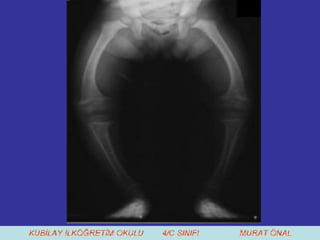

7. Ayrıca Güneş ışığından da yeterince faydalanmaya çalışmalıyız. Çünkü Güneş ışığının, kemiklerin gelişimine olumlu etkisi vardır.  D vitamini eksikliğinde raşitizm hastalığı ile karşılaşabiliriz .

7. Ayrıca Güneşışığından da yeterince faydalanmaya çalışmalıyız. Çünkü Güneş ışığının, kemiklerin gelişimine olumlu etkisi vardır. D vitamini eksikliğinde raşitizm hastalığı ile karşılaşabiliriz .